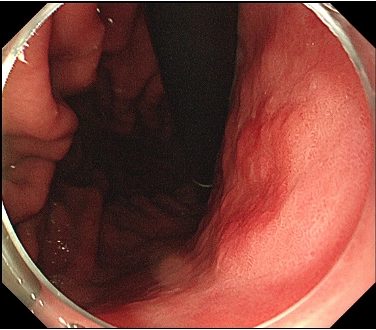

図2: 発赤調の隆起性病変(別角度・サンプル)

図2. 病変は発赤調の隆起性病変としてわかります。